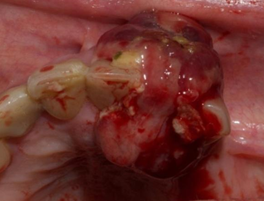

The upper and lower arches were partially edentulous. A localized tumor was detected in the left maxillary alveolar ridge. It involved teeth 2.1 to 2.3. It extended in the vestibular-palatal direction, from 1 cm inside the sulcus to 1 cm of the palatal mucosa. Tooth 2.2 was clinically missing. The lesion had defined boundaries of approximately 3 cm. It partially covered the crowns of the adjacent teeth, was oval, had an irregular and lobular surface, was consistent, bright red with violet areas and other yellowish-white areas. It had a bleeding texture, sessile implantation, and was painless. Grade 2 mobility of teeth 2.1 and 2.3 was also observed (figure 1and 2).

The patient was asked to come to the following appointment with a histopathological report of the nephrectomy performed and to coordinate the incisional biopsy of the oral lesion for the following week. The lesion had increased in size significantly by the second appointment (figures 4 and 5). The histopathological result of the nephrectomy performed was clear cell renal carcinoma.

Lesion evolution one week after evaluation, in the second appointment

A different strategy was used during the incisional biopsy: the clinician decided to remove the entire clinically visible lesion to control intraoperative bleeding and achieve proper hemostasis. Teeth 2.1 and 2.3 were extracted to help hemostasis. (figures 6 and 7).